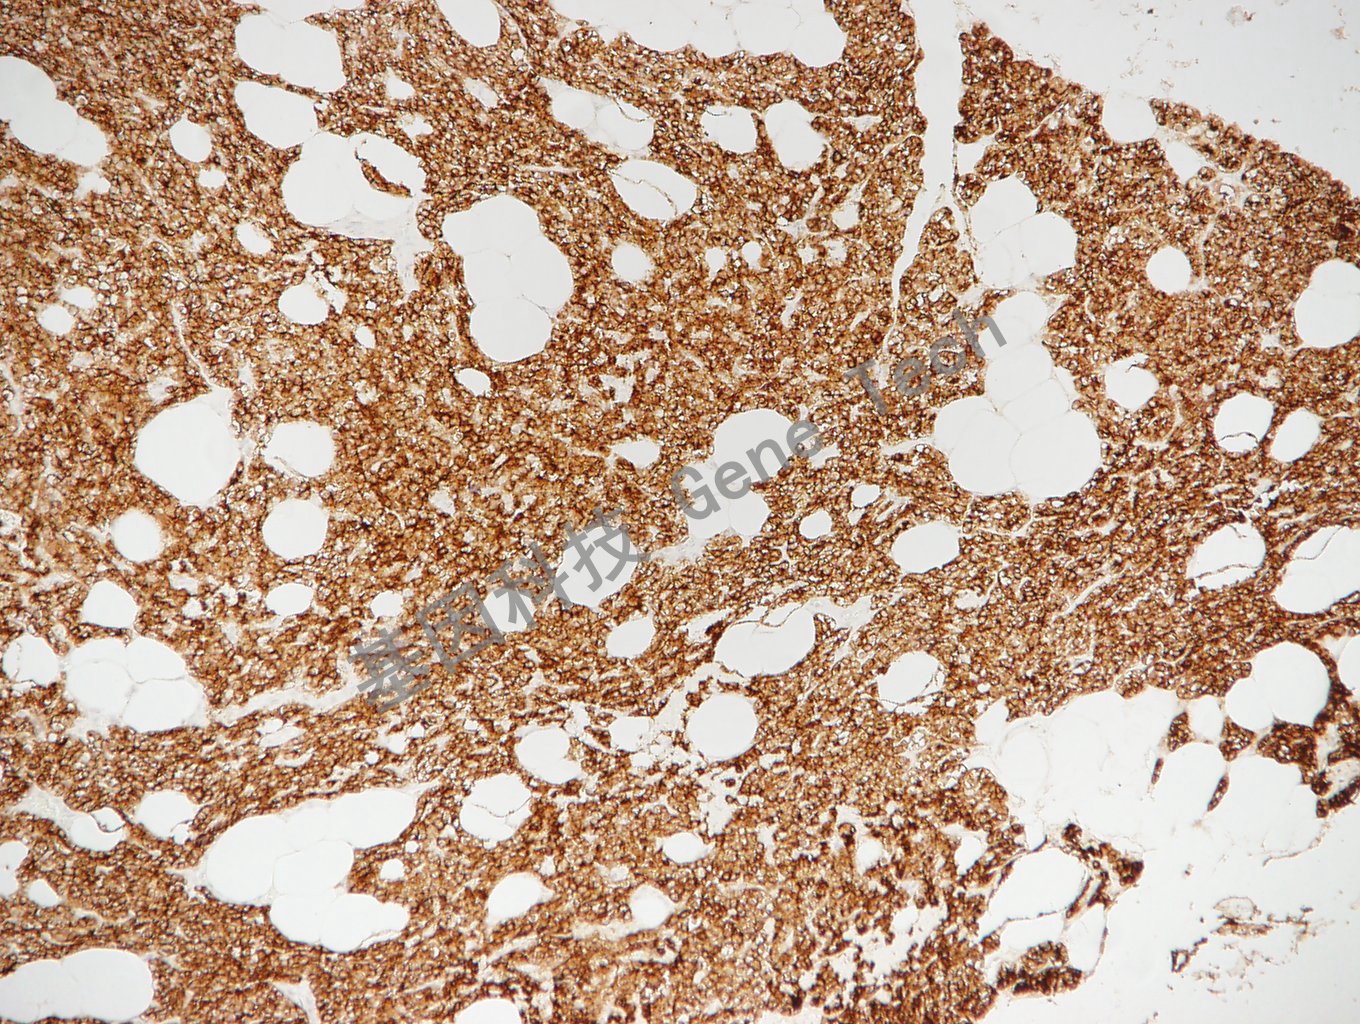

| 預(yù)處理:高pH熱修復(fù) | 陽性部位:細(xì)胞膜/細(xì)胞漿 | 陽性對照:甲狀旁腺瘤 |

| 甲狀旁腺瘤石蠟切片,用 PTH(GT2288)染色,細(xì)胞漿陽性,DAB顯色。 | ||